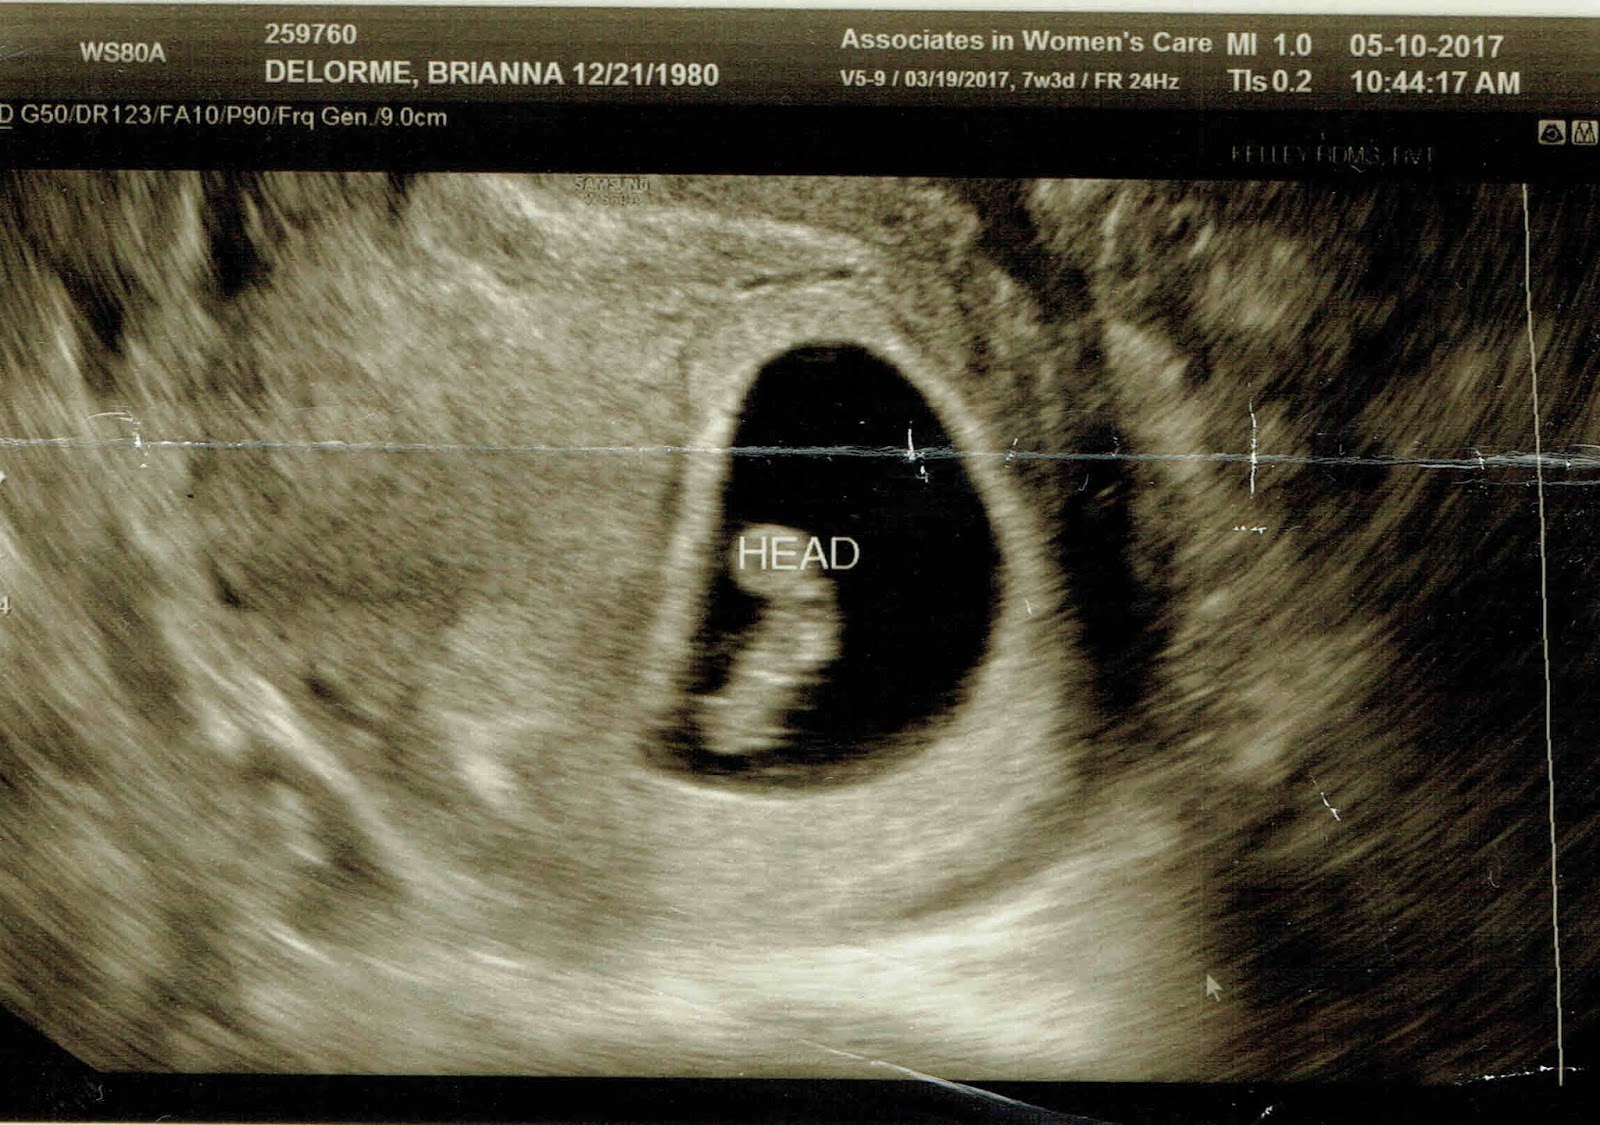

| First glimpse of our newest blessing |

We learned at my first ultrasound that our little bundle is due December 21st, which also happens to be my birthday. Talk about the best birthday present ever! I have always hated having a birthday so close to Christmas, and I feel a bit bad that this child will also go through the same thing. At least, I will be able to relate!